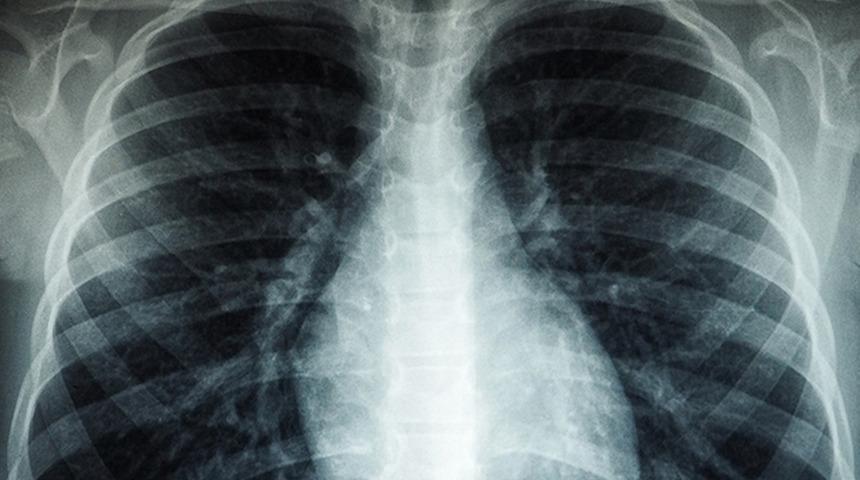

Örgütten yapılan yazılı açıklamada, 2021'de dünya genelinde 10 milyondan fazla kişinin tüberküloza yakalandığı ve bu oranda 2020'ye kıyasla yüzde 4,5 artış olduğu kaydedildi.

Açıklamada, geçen yıl, 1,6 milyon kişinin tüberkülozdan yaşamını yitirdiği ve 450 binin üstünde kişinin ilaca dirençli tüberküloza yakalandığı vurgulandı.

Tüberküloz vaka sayılarının, 2020'ye kadar sürekli düştüğü ancak 2021'den itibaren artışa geçtiği bilgisi verildi.

Kovid-19'un 2020'de dünya genelinde etki göstermesinin, tüberküloz vakalarını etkilediği ve küresel sağlık sisteminin tüm ağırlığını Kovid-19 ile mücadeleye vermesinin tüberküloz vakalarının teşhis ve tedavilerinin önüne geçtiği belirtildi.